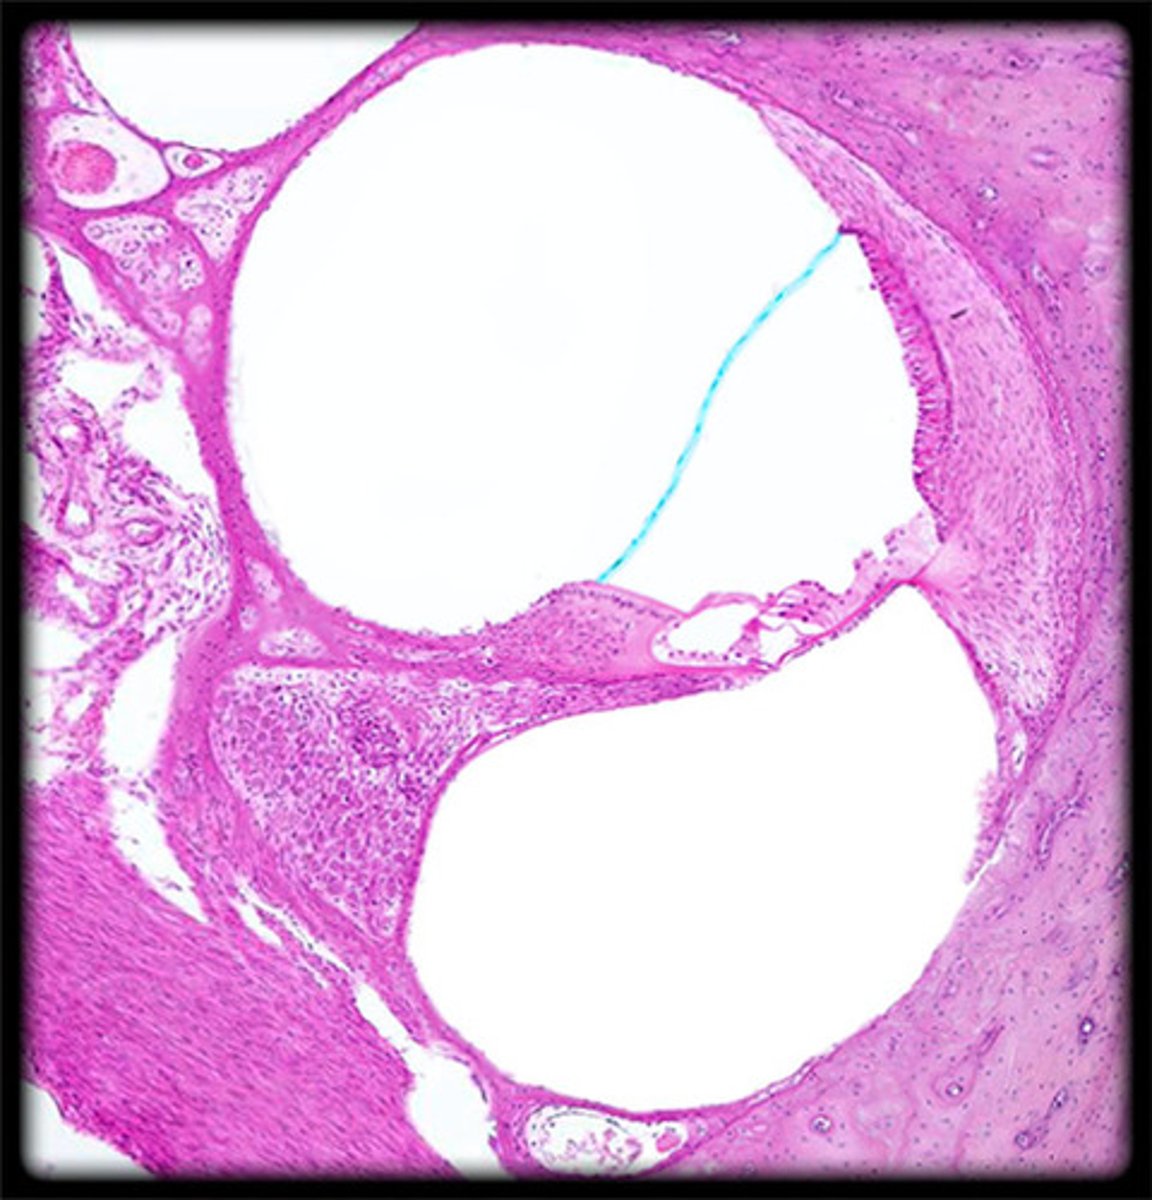

cochlea histology

scala vestibuli

contains perilymph

scala media

contains endolymph

scala tympani

vestibular membrane